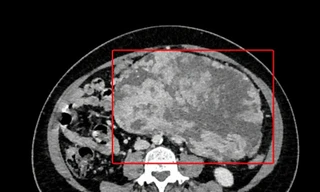

TPO - Ở giai đoạn đầu, ung thư thận thường diễn biến âm thầm, không gây đau hay triệu chứng rõ rệt, khiến nhiều người phát hiện bệnh khi đã ở giai đoạn muộn.